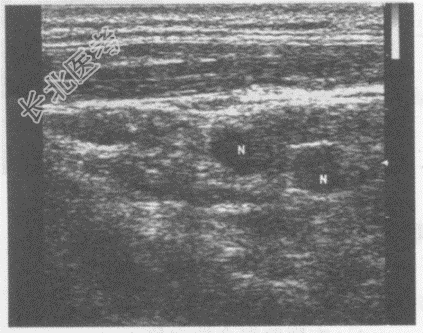

- 单项选择题男,44岁, 自述患慢性顽固性咽炎多年,久治不愈。超声综合描述: 右颈部可见数个长圆形低回声,边界清晰, 形态规则。超声提示:

A、右颈部淋巴结转移瘤

B、右颈部淋巴结结核

C、右颈部正常淋巴结声像图

D、右颈部多发肿大淋巴结(慢性炎性肿大)

E、右颈部淋巴管炎